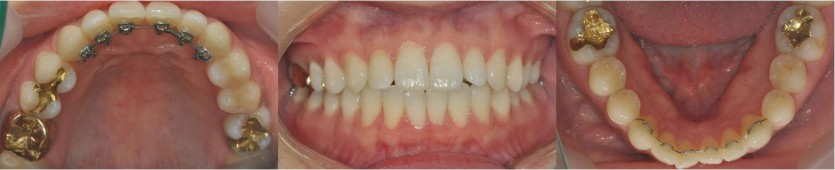

6개월에 걸쳐 길쭉해 보이는 앞니를 개선한 사례입니다.

교정치료 중에 웨딩 촬영 일정이 있으셨기에 장치가 겉으로 보이지 않는 설측교정으로 진행하였습니다.

설측교정으로 진행 시, 위 사진과 같이 장치가 겉으로 보이지 않는다는 장점이 있습니다.